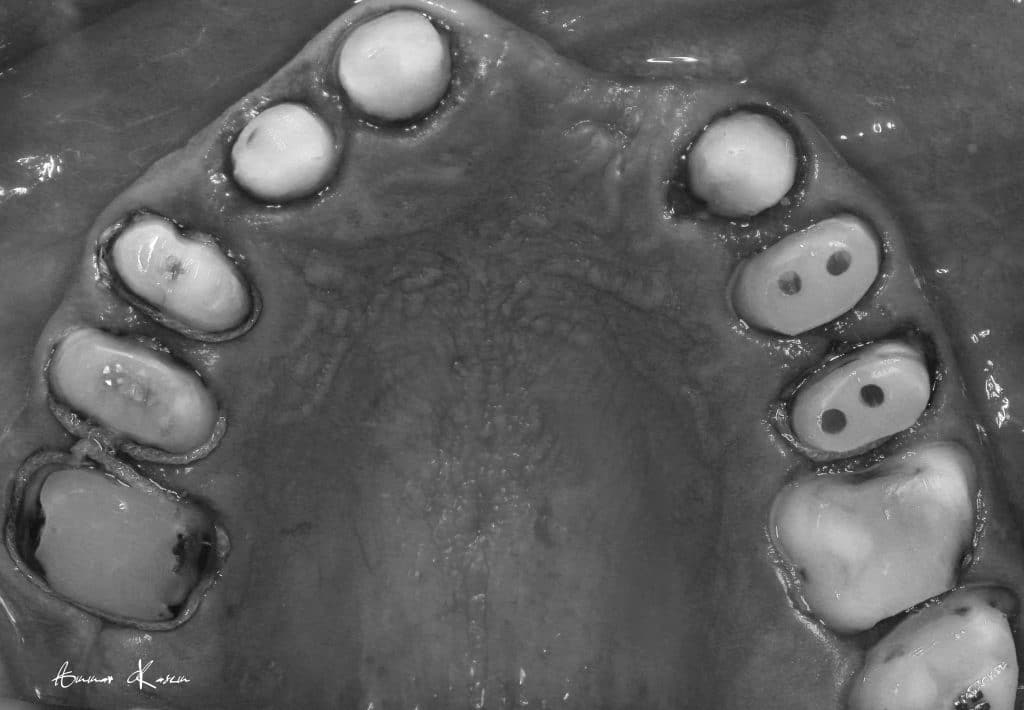

Temporization phase including;

5- 1st mock up ( edge to edge ) for 2 months

6- 2nd mock up ( Normal class I) for 3 months

7- Preparation phase through half arch technique to preserve the vertical dimension